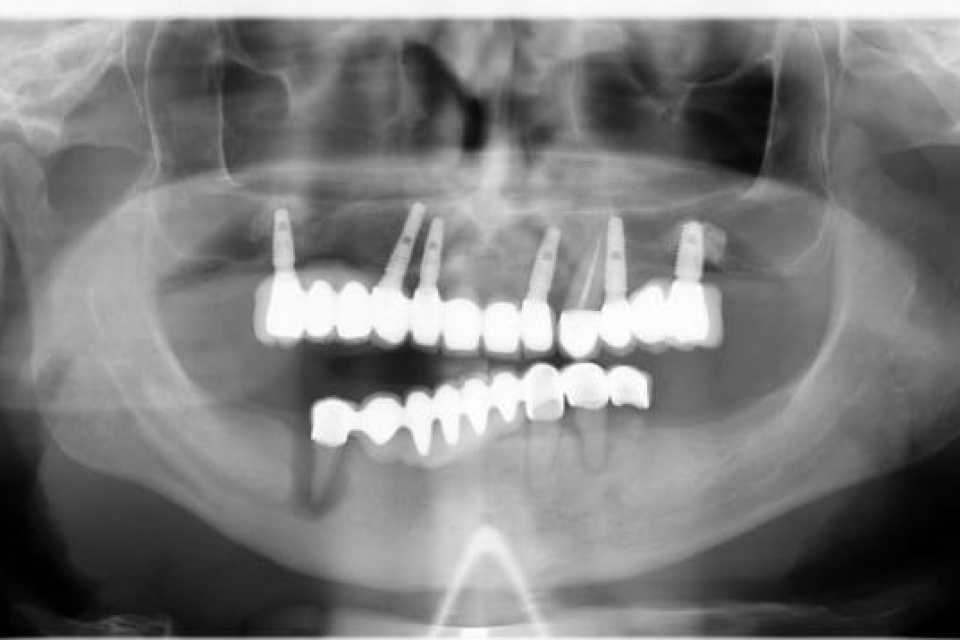

Pacientul în vârstă de 55 de ani, s-a prezentat în cabinet cu o lucrare dentara metalo ceramica ,la nivelul mandibulei, de 9 elemente pe 4 dinti parodontotici irecuperabil.

Împreună cu pacientul am hotărât inserarea a 5 implanturi dentare Mega Gen Anyridge, cu ajutorul cărora într-o prima fază am protezat a doua a zi cu o lucrare provizorie, astfel încât la 2 luni de la intervenție să realizăm lucrarea finală de 12 elemente ceramica pe zirconiu.